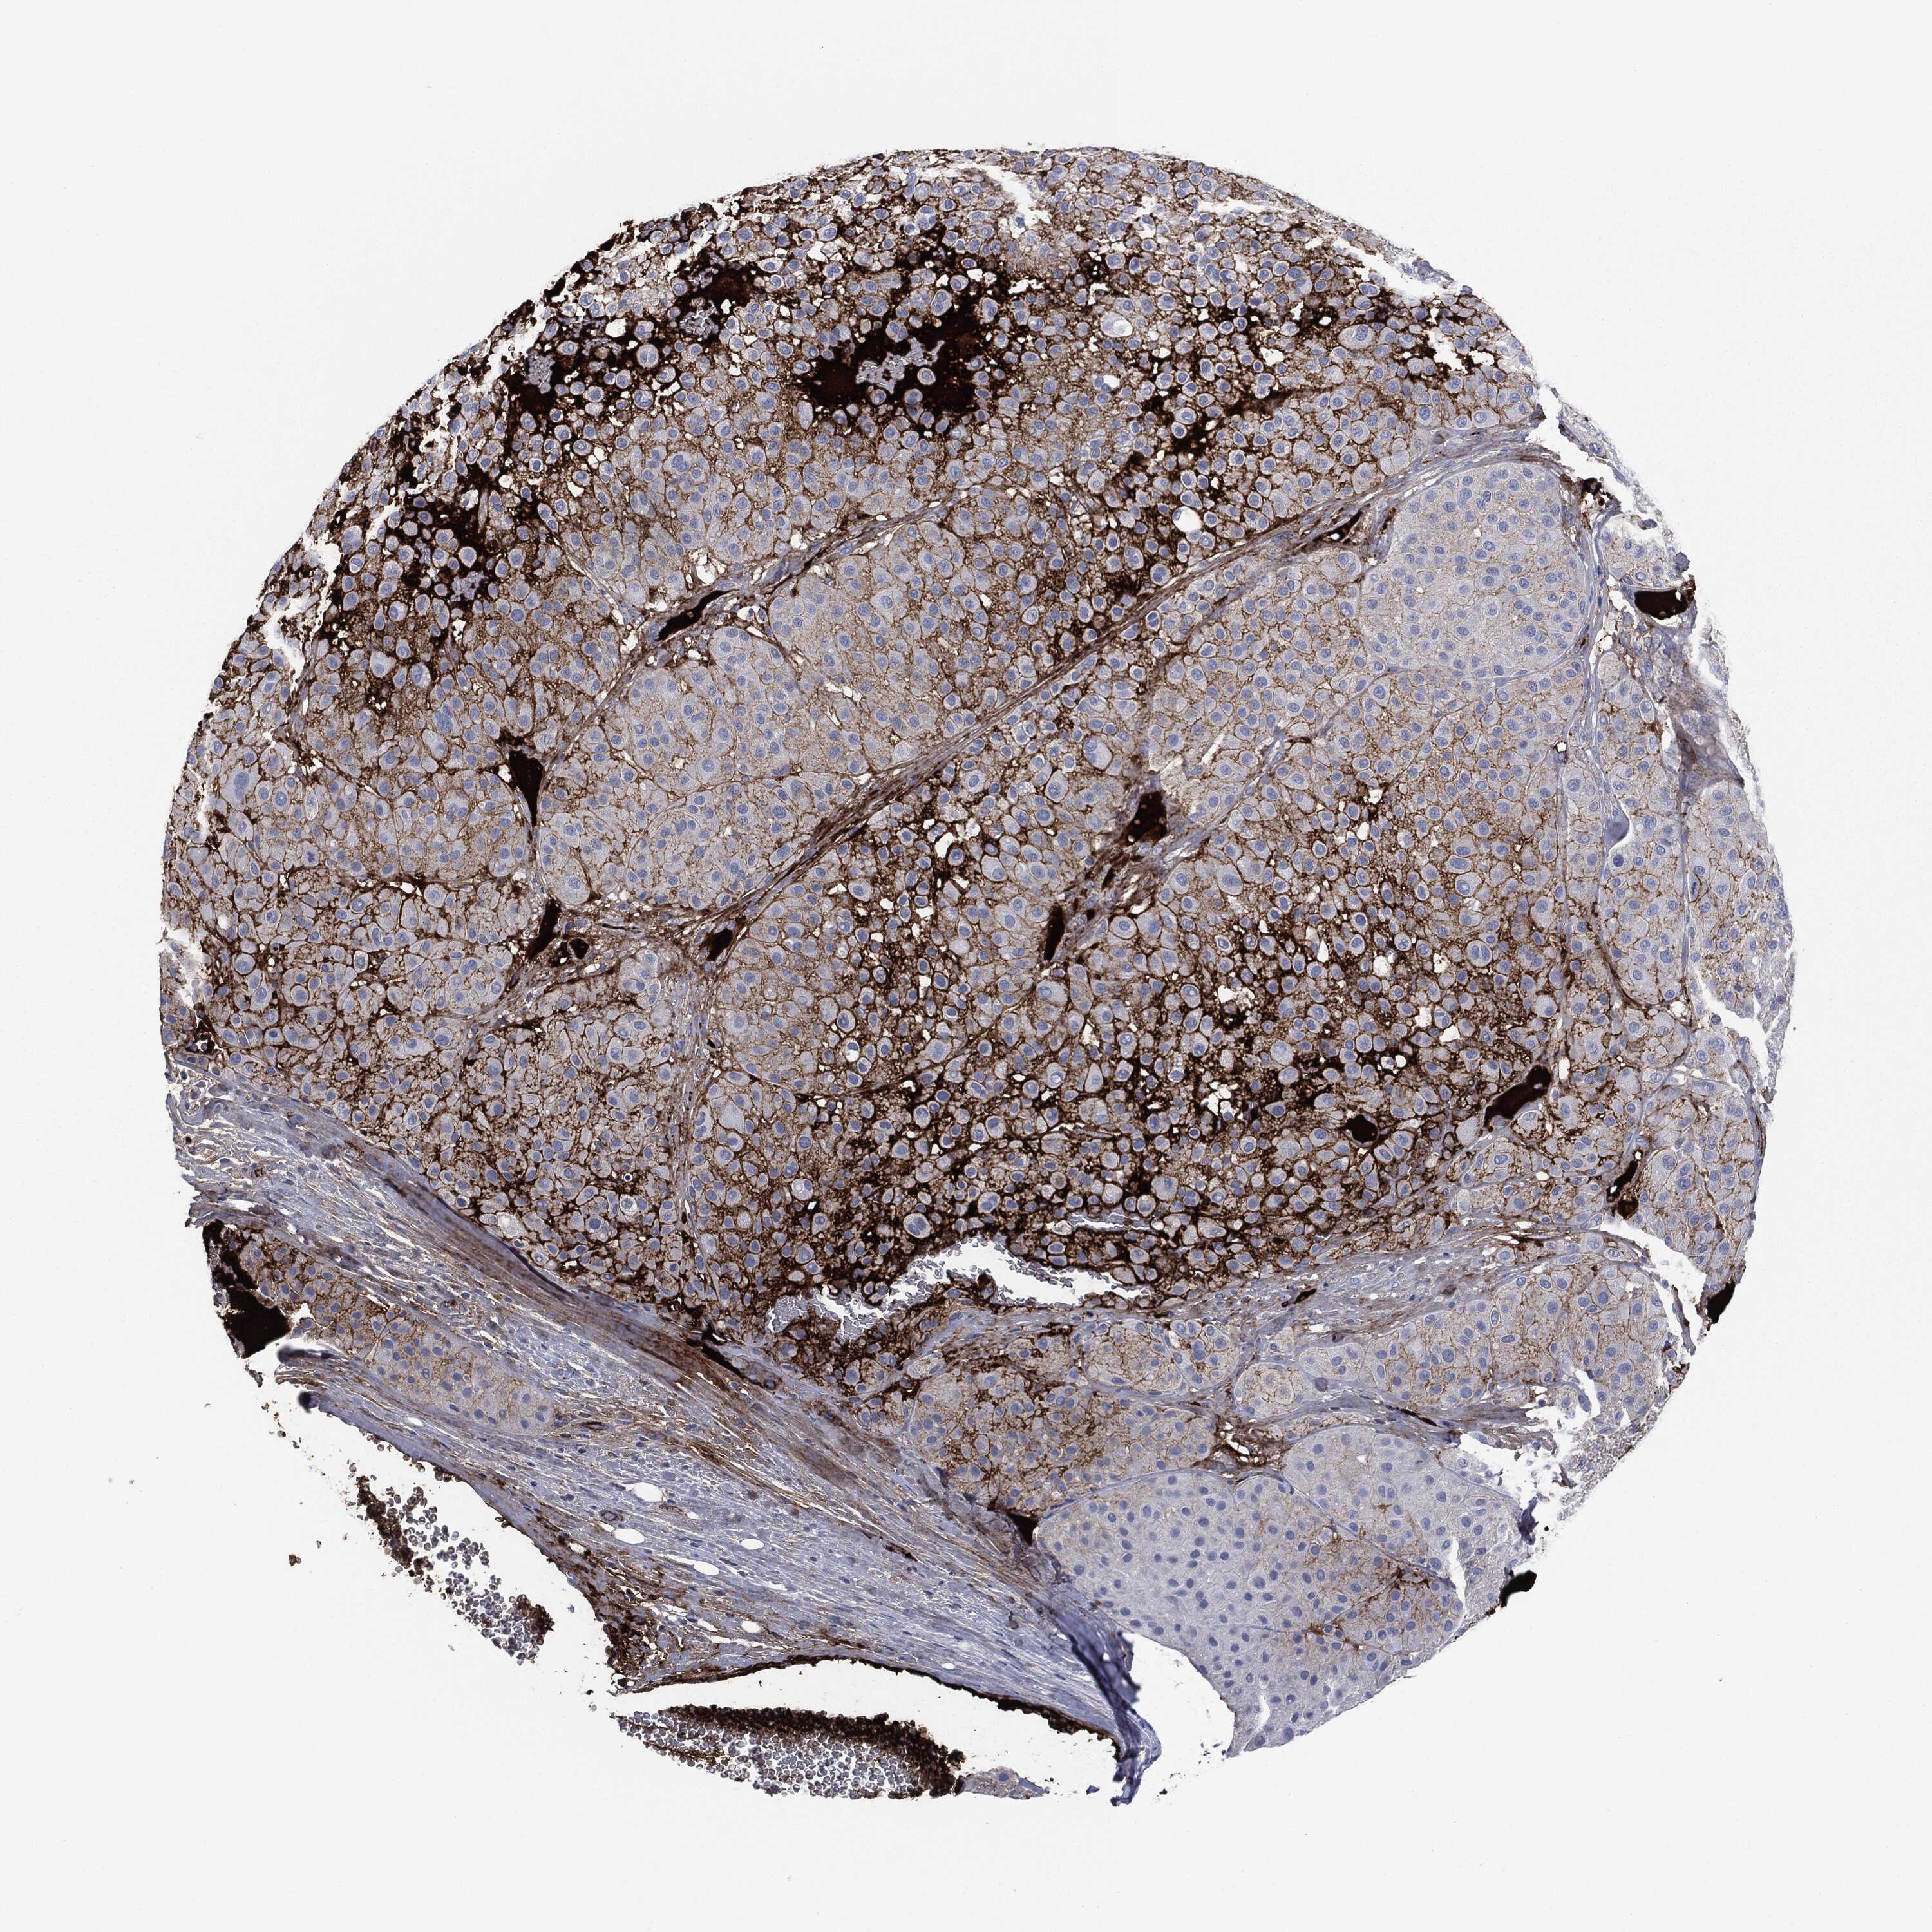

MELANOMA - Protein expressioni

A mouse-over function shows sample information and annotation data. Click on an image to view it in a full screen mode. Samples can be filtered based on level of antibody staining by selecting one or several of the following categories: high, medium, low and not detected. The assay and annotation is described here.

Note that samples used for immunohistochemistry by the Human Protein Atlas do not correspond to samples in the TCGA dataset.

Antibody stainingi

Antibody staining in the annotated cell types in the current human tissue is reported as not detected, low, medium, or high, based on conventional immunohistochemistry profiling in selected tissues. This score is based on the combination of the staining intensity and fraction of stained cells.

Each image is clickable and will lead to virtual microscopy that enables deeper exploration of all samples and also displays staining intensity scores, fraction scores and subcellular localization as well as patient and tissue information for each sample.

HPA049793

CAB016070

CAB080297

CAB080298

CAB080299

Malignant melanoma, NOS

Malignant melanoma, Metastatic site